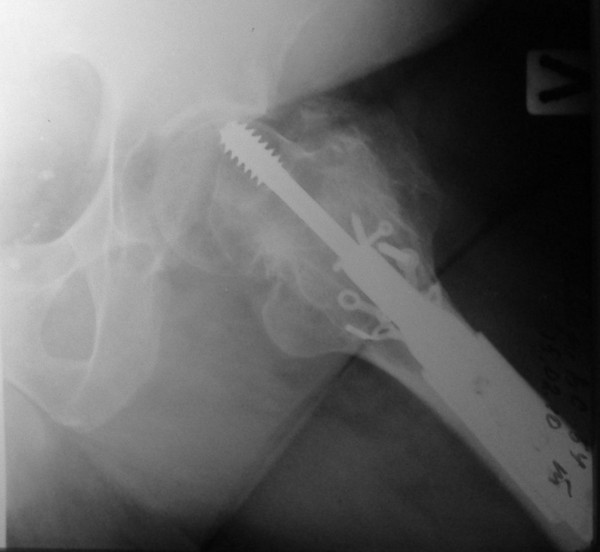

Уважаемые коллеги, каково ваше мнение по поводу необходимости удаления металлоконструкций в данном случае - мужчина, 53 лет, сопутстувующая патология - схараный диабет 2 типа, впервые выявленный, ГБ 1-2 ст., хр.калькулезный холецистит, хр.гепатит. Операция произведена в январе 2009 г. через 18 сут. после получения травмы.